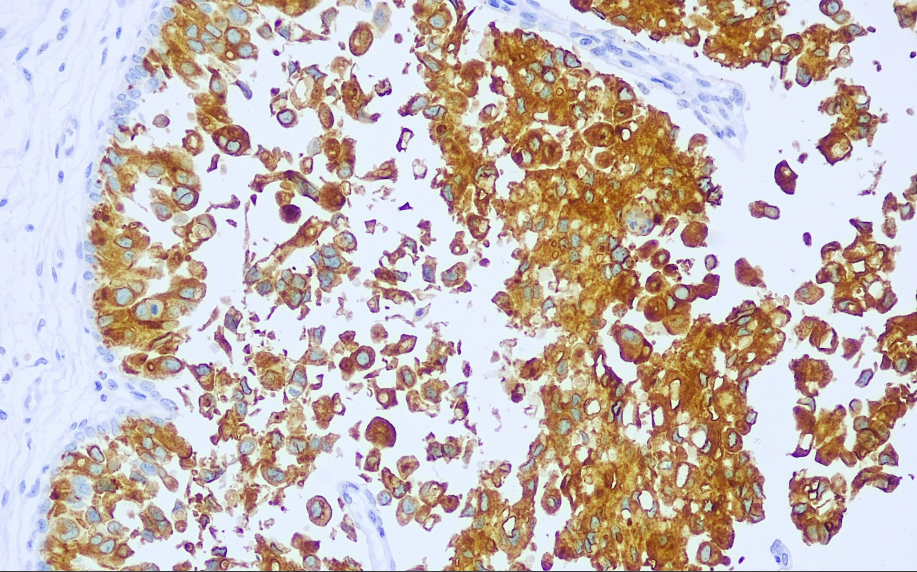

Positive control: Urothelial carcinoma

Roplakins (UPs) are a family of transmembrane proteins involved in the differentiation of bladder epithelial cells, comprising four types: Ia, Ib, II, and III. In non-tumorous urinary tract epithelium, they are expressed in the luminal surface of the superficial layer in the form of 16-nm particles. Studies have shown that these four glycoproteins are exclusively present in urothelial transitional epithelium and are virtually absent in other tissues. The expression of uroplakins in bladder transitional cell carcinoma is correlated with the degree of differentiation of bladder cancer, with higher expression levels observed in more differentiated tumors. Uroplakin II, as a highly specific antibody, is highly useful in the differential diagnosis of tumors of urothelial origin.

Uroplakin II antibody reagents can specifically bind to the Uroplakin II molecular antigen. Immunohistochemistry kits containing Uroplakin II antibody reagents are suitable for the auxiliary diagnosis of tumors originating from the urinary tract epithelium.